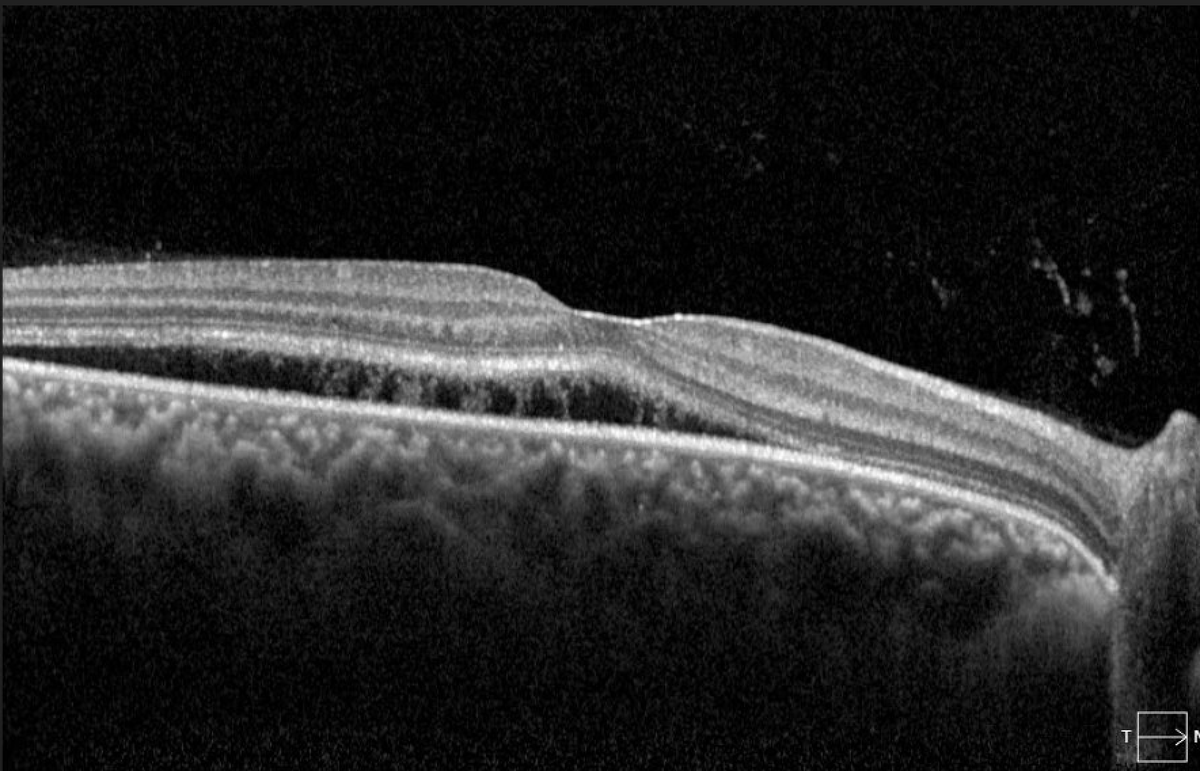

My first gift from a patient. Fight the good fight, because even if you don’t win, your patients will know they didn’t have to fight alone. We are the collective lighthouse guiding patients during the blinding tempest of disease. #ophthalmology #attending